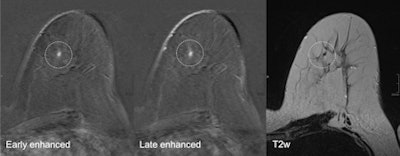

Mammography is not the only place where errors occur: Breast MRI sees its fair share as well. Use of the modality is on the rise due to its sensitivity and specificity; however, technical difficulties in association with a lack of expertise in reading breast MR exams can lead to misinterpretation and errors, according to Dr. Federica Pediconi from the department of radiological sciences at the University of Rome "La Sapienza" in Italy.

"Breast MRI is technically demanding, requiring excellent fat saturation, high spatial resolution, and rapid performance of postcontrast sequences," she said. "Common causes of false-positive diagnoses are represented by artifacts that can be related to the patient or to technical parameters."

Other factors of imaging interpretation error can be related to the presence of background parenchymal enhancement that can reduce the diagnostic accuracy and insufficient history or lack of practice in reading MR images. During her presentation, Pediconi will provide an overview of different types of diagnostic errors as well as the way to avoid them and handle them.